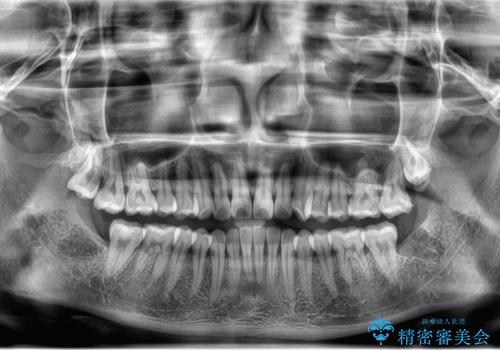

左下の親知らずが腫れた感じがする。

- 左下親知らずが腫れてる感じがして痛いとの事で来院。

抜歯を希望されたので抜歯術を行いました。

親知らずを長年放置すると手前の歯が虫歯になるリスクがあがります。

虫歯になる前に親知らずは抜歯することをお勧めします。